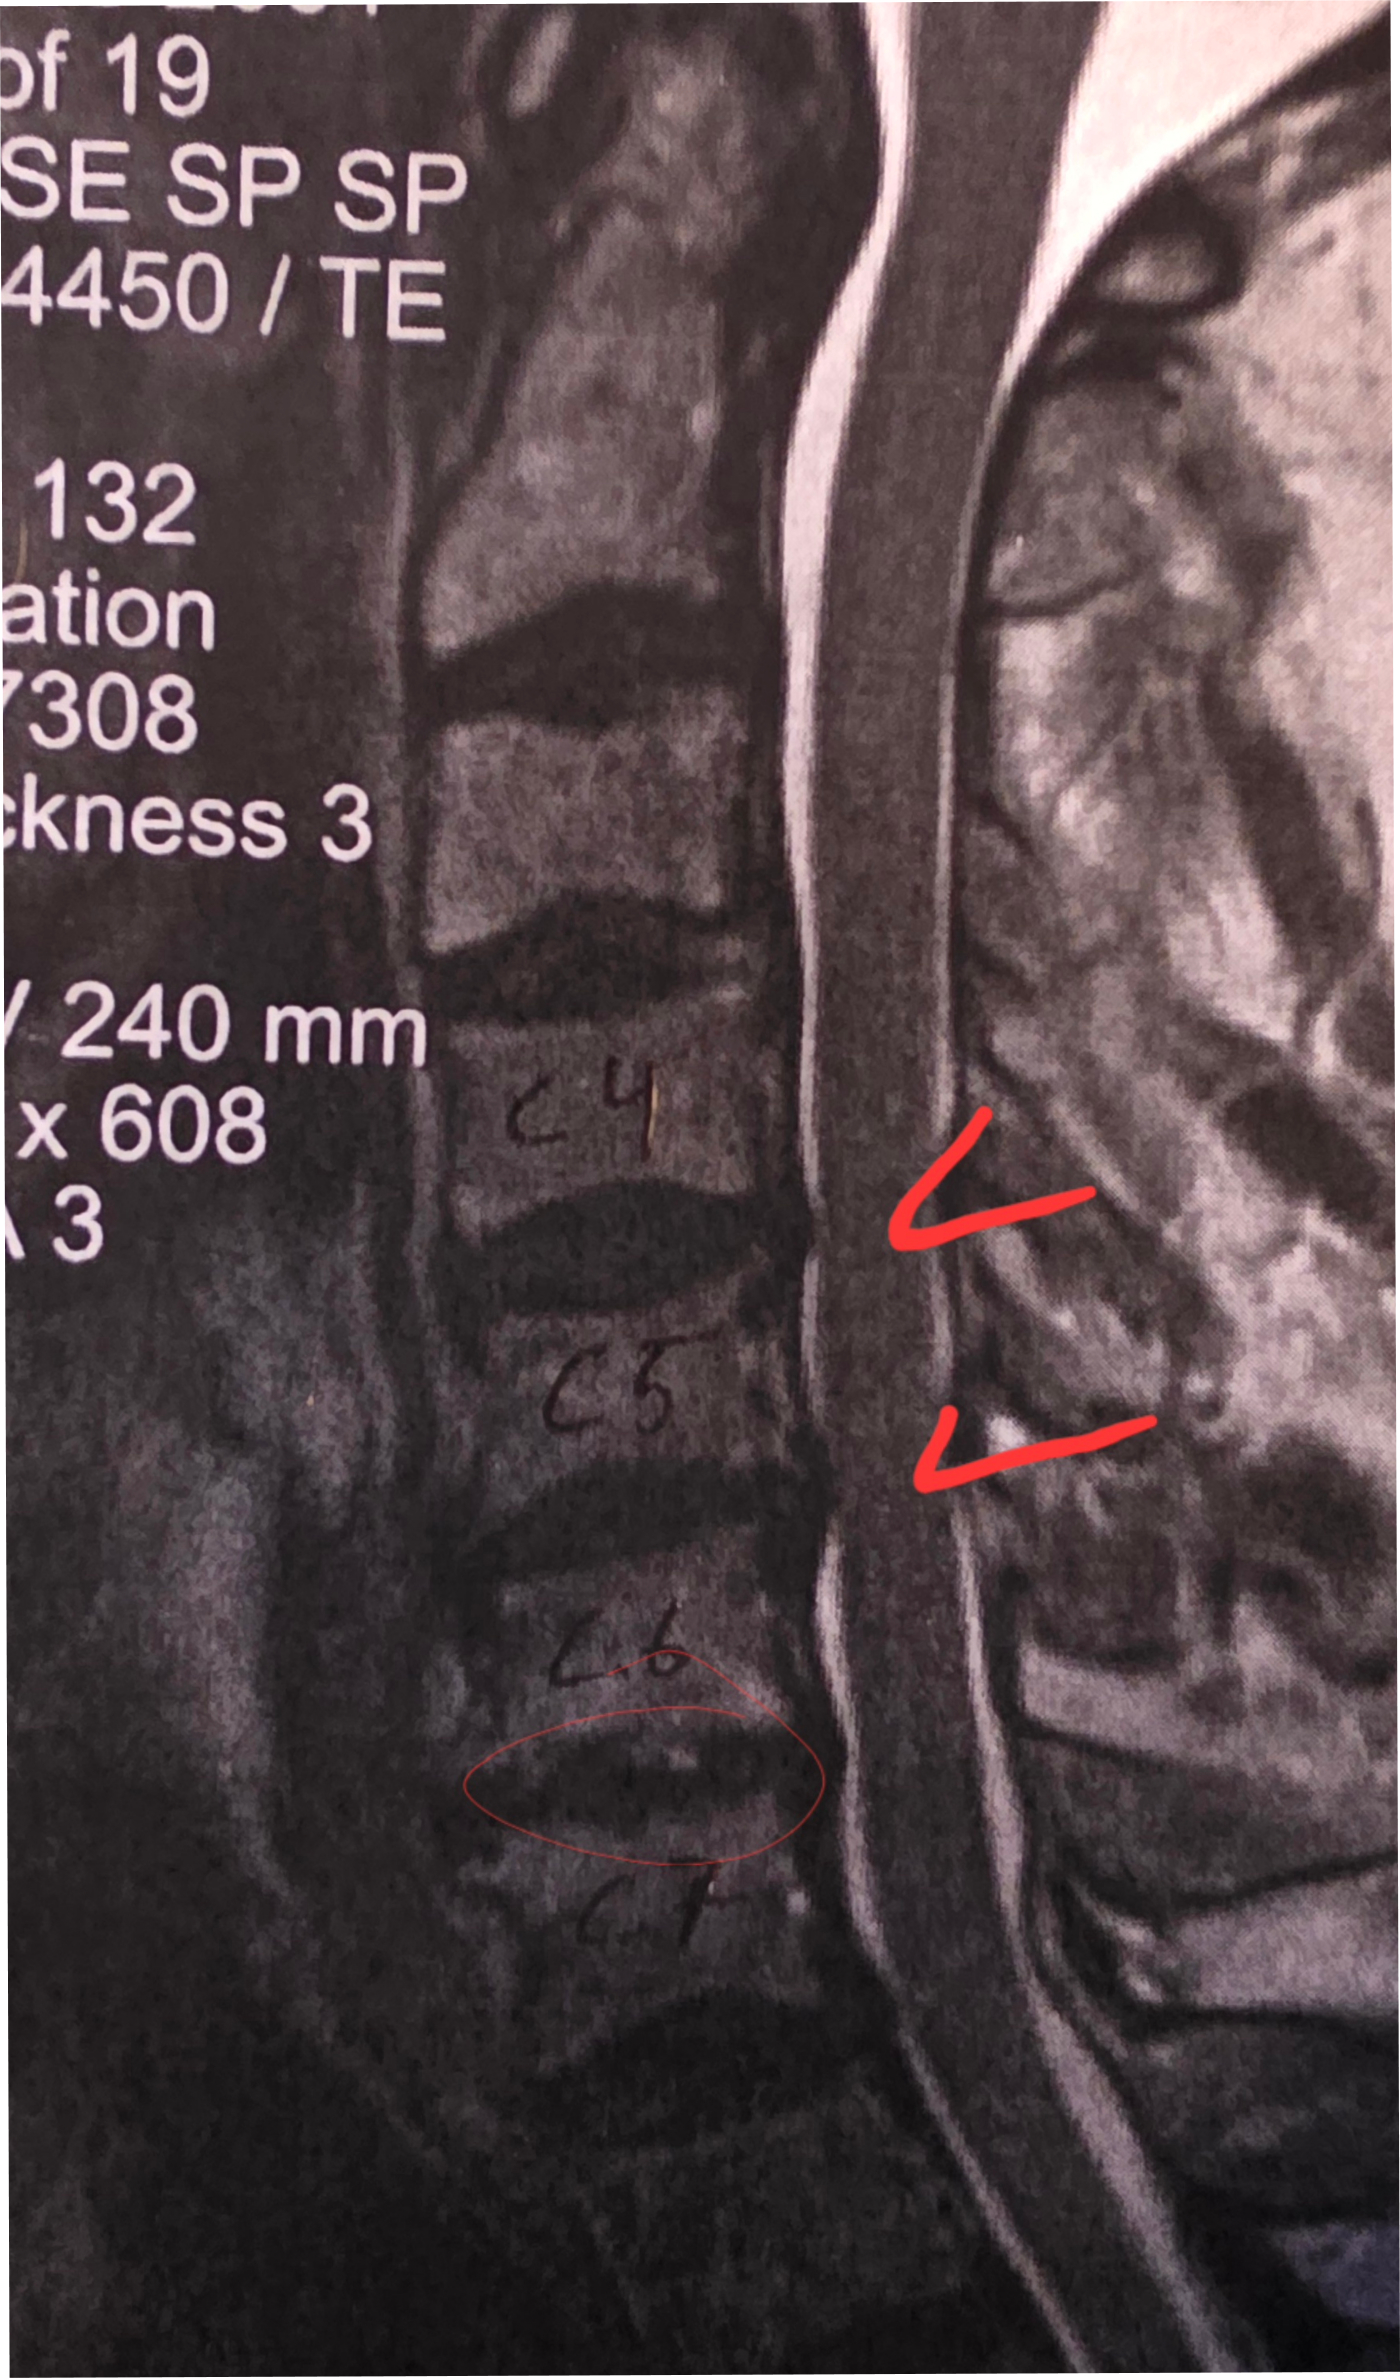

The time has come to take a break from the shop for a few weeks as I have neck surgery coming up in a few days. The surgeon will be fusing C4, C5, C6, and C7 vertebrae in hopes of releasing encapsulated nerves so that my left shoulder can work again. For the past 2.5 months I lost use of the shoulder 100%: best way to picture it is to glue your elbow to your rib and you can only mover the lower arm anywhere it wants, kind of like a T-Rex. :-) Otherwise my arm has not been able to move forward, outward, or upward. The good news is that I have had zero pain…the only time it’s been real fun is when I lost my balance twice to my left and had no arm to stop me from falling into the wall or whatever was in my path. I pitied those objects as I’m a big lug. No other harm done, except maybe that which I hit. ***NEW PAGE: “Gift Ideas”, which are non-flute items I’ve created…I love various forms of art and photography, and I have a 2026 calendar of my wildflife photography as well as 2 different sets of five notecards from Haywood County. One is of scenic views, and the other is of wildlife. The cards are 5” x 7”, providing a good amount of space for writing longer notes. These have been only recently produced, so have not yet hit the market, so to speak. Admittedly I’m still trying to nail down the price since the price of shipping is such a bugger anymore, but I’ll post that as soon as I can find affordable mailers and have the shipping priced out. The calendar features only five critters from Haywood County, the rest from other places. The cover is one of my favorite animals of all, the Barred Owl, this one sitting quite often right by home, All pictures enlarge nicely when you click on them, so you can see more of the details. The cards have additional information on the back of each, FYI. # # # I’m doing my best to stay on top of the MOUNTAINOUS emails full of too much spam, but if you don’t hear from me in a timely manner please gently nudge me again. The amount of emails is stupid, and building constantly…I clear out up to 200 junk emails every day, and heaven forbid a skip a day or two. Eegads… Knowing me, I’ll be sneaking in to the shop even if to try and clean it up and organize things better as I convalesce. Lord knows there is almost no limit to what needs to be done down there, and I have some stunning wood I can’t wait to get cutting. On top of more Spalted Tamarind, I have some figured Cheche and a new wood that I’d never heard of, Muirapixuna. It’s very much like chocolate brown Ebony, but a totally different species, from Brazil. Stay tuned! Browse and enjoy! Email with any questions. Bob Child weatherflute@yahoo.com